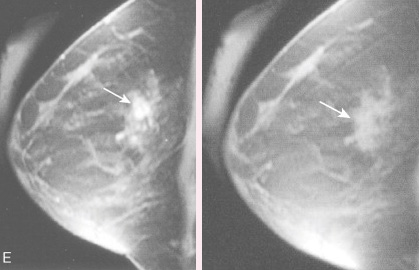

Long-term use of constrictive bras, hormone replacement therapy, disrupted circadian rhythm, air pollution, and sedentary lifestyle do not directly destroy breast tissue. Instead, they cause persistent accumulation of estrogen metabolites, necrotic cells, and inflammatory factors within lymphatic vessels, resulting in irreversible blockage. Clinical data show that women over 50 have an average lymphatic flow rate of only 27% compared to younger ages. Localized induration, increased mammographic density, and unexplained masses are all typical manifestations of this chronic obstruction. Conventional interventions only alleviate surface symptoms and cannot remove deep deposits.